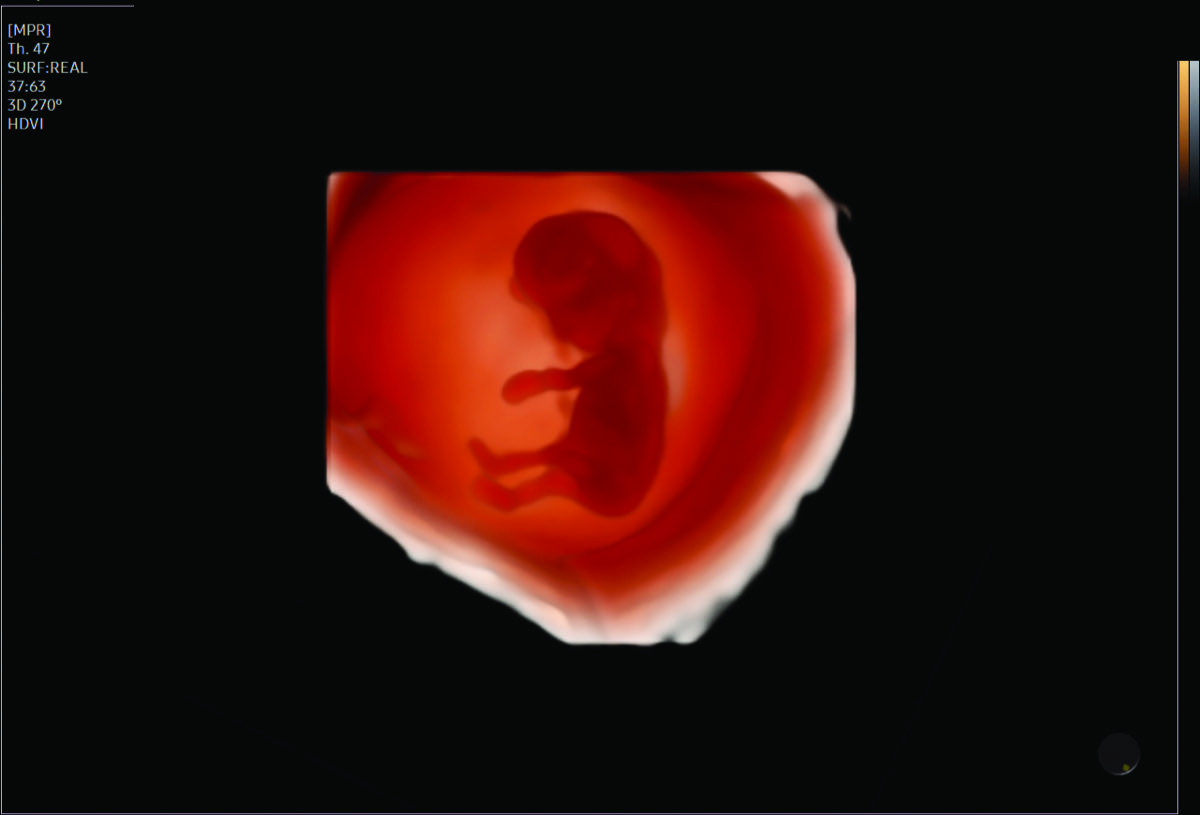

- Multiple births